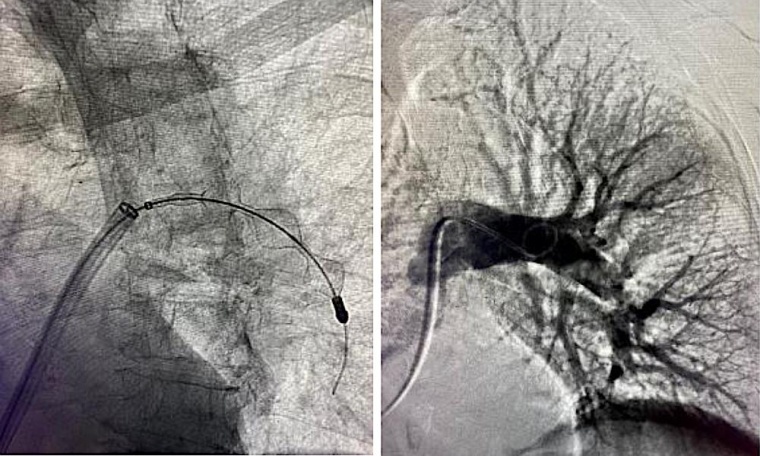

Bei dem neuen System wird ein flexibler, rund acht Millimeter dünner Schlauch per Katheter in örtlicher Betäubung über die Leistenvene durch das Herz bis in die Lungenarterie vorgeschoben. Dabei ist höchste Vorsicht nötig, um die sensiblen Strukturen nicht zu beschädigen. Per Röntgenaufnahmen wird kontrolliert, ob der Schlauch das Gerinnsel präzise erreicht hat; mit einem Drahtgeflecht ziehen die Ärzt*innen dann das Gerinnsel in den Katheter, während mögliche Fragmente direkt vor Ort eingesaugt werden. „Wir konnten sofort nach der Entfernung des Gerinnsels beobachten, wie die Sauerstoffsättigung im Blut unserer Patientin deutlich anstieg“, sagt Noory. „Schon gegen Ende der Behandlung berichtete sie, dass sie viel besser Luft bekommt.“ Bereits wenige Stunden nach dem Eingriff konnte sie auf eine Normalstation verlegt werden, nach wenigen Tagen wurde sie nach Hause entlassen.